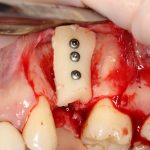

Далее, можем приступить к установке имплантатов. Разумеется. по хирургическому шаблону:

Последняя картинка даёт представление о том, какой объем костной ткани мы «нарастили».

Поскольку принимающее ложе и аутокостный блок конгруэнтны, мы можем отказаться от использования барьерной мембраны. Она не нужна.